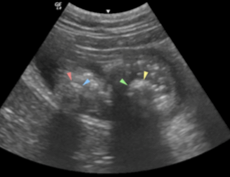

“When Kathmandhu arrived, the staff immediately called in our specialist in diagnostic imaging Dr Ian Jones - who was working remotely that morning - and he cycled into the hospital to perform an abdominal ultrasound scan which revealed the blockage.